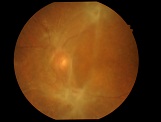

今日は水晶体亜脱臼による緑内障発作の患者様がいらっしゃり、お昼休みに緊急手術をさせて頂きました。

先日ハードレンズを処方した方の写真です。

先日ハードレンズを処方した方の写真です。